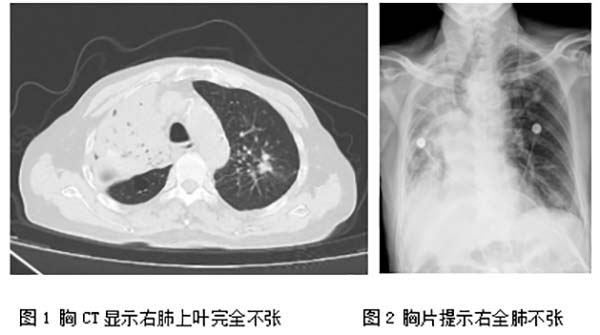

81岁的刘大爷既往身体健康,但3个月前突然出现咳嗽、咯血,病情迅速恶化,出现呼吸衰竭,当地医院给予紧急气管插管后转诊到清华大学附属垂杨柳医院呼吸与危重症医学科。CT检查发现右侧主支气管内新生物,阻塞气道,来源于右肺上叶,导致右上肺不张(图1),经过气管镜下切除病变,右主支气管再通。病理结果提示肺肉瘤样癌,临床分期为cT3N3M0,IIIc期。第一次镜下介入治疗后,刘大爷的症状明显缓解。考虑到患者高龄,家属拒绝接受其他治疗方案,选择出院保守观察。

2025年5月22日深夜,距第一次镜下介入治疗仅仅10余天,患者再次出现突发喘憋加重,由120紧急转运至清华大学附属垂杨柳医院急诊科。在高流量吸氧80%条件下,患者静息氧饱和度仅能维持在80-85%左右,床旁胸片显示右肺完全不张可能(图2),呼吸与危重症医学科介入团队评估后,判断肿瘤进展阻塞气道可能性大,决定立即进行急诊手术准备。入手术室时患者血氧饱和度仅有68%,伴有神志淡漠,意识恍惚。全麻后呼吸介入团队马上进行进镜探查,发现10余天前已被大部分切除的肿瘤再次疯长,右主支气管再次被肿物完全阻塞。呼吸介入团队用电圈套器、电刀、冷冻冻切等多种方法,再次迅速打通了气道,术后患者氧饱和度已恢复至97%(见报道【垂医MDT】生命之光,再度点亮)。